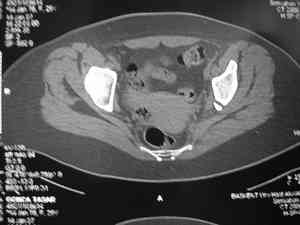

Dear group,30 years age female MVA front seat, head trauma + post column left acetabular fracture, 2.5 weeks skeletal traction. She is now conscious but still confused without any surgical treatment for brain edema.

Latest X rays and CAT is attached.Fracture within first 1.5 cm from the weight bearing dome, although AP and Obtrator oblique good, iliac oblique view reveals some displacement.I'm not sure that nonsurgical treatment will be OKHüseyin DemirorsBaskent UniversityDept of Orthopedics and TravmatologyAnkara TURKEY

My vote, given the amount of displacement on the iliac oblique and CT scan, would be for ORIF thru a posterior approach ASAP - these get pretty tough

CT scan taken 5 days ago and radiographs taken today

I may get beat up for this, but I see very little displacement that concerns me on the CT. The radiograph is more concerning. I suspect it could look better, and the gap made smaller on CT. Not sure if it will affect outcome. I might give it a shot and try to see what could be done.